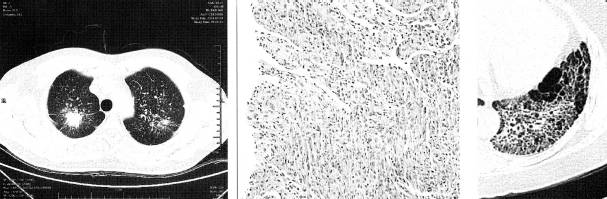

(1)周围型肺癌基本X线表现为肺内孤立的球形灶,不同组织类型的肺癌在大小、 医学百科网 | YxBaike.Com

密度、边缘形态及瘤体周围特点有一定差异。CT的优势在于可显示瘤体内密度、坏死、血供特点及临近结构浸润情况。除边缘凹凸不平,呈分叶征外,常可见边缘毛刺、瘤周血管集束征、胸膜凹陷征、内部空洞形成,多壁厚薄不均,内缘凹凸不平或见壁结节。无或少有气液平为其特征(图2)。增强检查病灶可见明显强化,CT值增加25Hu以上。高度提示 肺癌。 医学百科网 | YxBaike.Com

炎性假瘤是肺部慢性炎症的一种特殊形态,本质是增生性炎症,病理上由多种细胞组成 的肉芽肿并有纤维化增生形成的一肿瘤样团块,可发生在两肺任何部位,多位于肺边缘部及靠近叶间裂(图7)。病灶多为球形、类圆形团块影,密度均匀,边缘清晰或模糊,多有 长毛刺,临近胸膜增厚粘连常见,常有“桃尖征”的特征性表现。增强扫描时包膜强化,其 环形强化边缘呈连续性,无中断,此亦为特征性表现,可以与肺癌鉴别。但不典型炎性假瘤 CT征象可多样化:多灶性,多态性,有的可有空洞和钙化,边缘毛糙不规则,内部密度不 均,可有强化。肿块可呈分叶状与周围型肺癌非常相似(图8)。但是胸膜边缘的炎性假 瘤CT表现有其特征:软组织肿块中偶可见偏心性空洞,病灶经多方位重建可呈长条样改 变,边缘有收缩、牵拉现象。这是由于胸膜因炎症刺激部分有增厚与假瘤合成软组织肿块, 其边缘也可被牵拉撑起围成一个透亮区,形成所谓“偏心空洞”。

常位于上叶尖后段、下叶背段,因肺泡壁破坏,无空泡征或支气管充气征,增强检查内 部为低密度无增强影,肉芽肿成分为主亦可见增强。病灶边缘光滑,一般无分叶及毛刺,少 许有多个增殖性病灶融合形成者,可不规则成分叶状。病灶内多可见钙化,CT值多高于 160Hu、周边多有卫星灶,局部胸膜增厚多见,长期随访观察,一般增长不明显,病程较 长,肺内常另有散在性结核病灶。但病灶如表现不典型,呈孤立肿块影,有时与肺癌难以鉴 别(图9)。 医学百科网 | YxBaike.Com